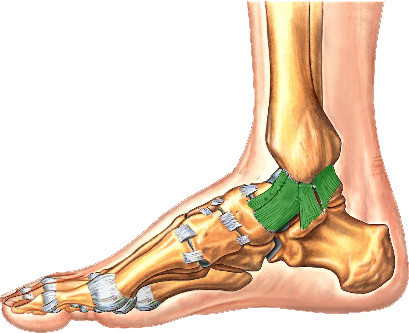

What is this structure?

Deltoid ligament of ankle